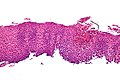

Eosinophilic esophagitis. H&E stain. | |

| LM | mucosa with abundant eosinophils (60 per mm*mm), basal cell hyperplasia (three cells thick or >15% of epithelial thickness), papillae elongated (reach into the top 1/3 of the epithelial layer) |

- Mucosa with abundant eosinophils - the consensus on eosinophils per area is 60/mm*mm.[3]

- Basal cell hyperplasia.

- Three cells thick or >15% of epithelial thickness.

- Papillae elongated.

- Papillae that reach into the top 1/3 of the epithelial layer - definition for GERD.[9]